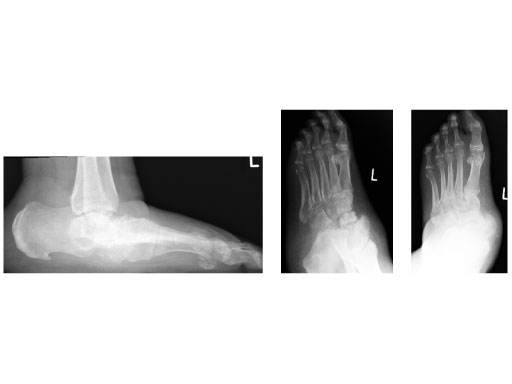

42-year-old, female with severe insulin-dependent diabetes mellitus (IDDM); Charcot foot, wheel chair since 1 year.

Case provided by Hermann Bail, Berlin, DE